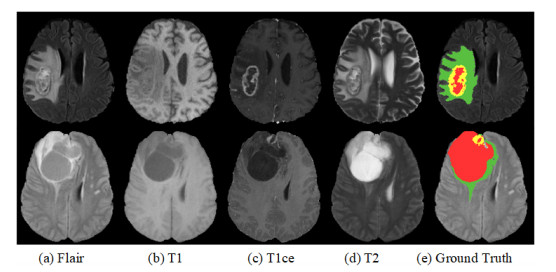

• Computer-aided brain tumor segmentation using magnetic resonance imaging (MRI) is of great significance for the clinical diagnosis and treatment of patients. Recently, U-Net has received widespread attention as a milestone in automatic brain tumor segmentation. Following its merits and motivated by the success of the attention mechanism, this work proposed a novel mixed attention U-Net model, i.e., MAU-Net, which integrated the spatial-channel attention and self-attention into a single U-Net architecture for MRI brain tumor segmentation. Specifically, MAU-Net embeds Shuffle Attention using spatial-channel attention after each convolutional block in the encoder stage to enhance local details of brain tumor images. Meanwhile, considering the superior capability of self-attention in modeling long-distance dependencies, an enhanced Transformer module is introduced at the bottleneck to improve the interactive learning ability of global information of brain tumor images. MAU-Net achieves enhancing tumor, whole tumor and tumor core segmentation Dice values of 77.88/77.47, 90.15/90.00 and 81.09/81.63% on the brain tumor segmentation (BraTS) 2019/2020 validation datasets, and it outperforms the baseline by 1.15 and 0.93% on average, respectively. Besides, MAU-Net also demonstrates good competitiveness compared with representative methods.